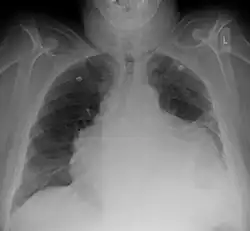

Chest X-ray showing a massive pericardial effusion: Water bottle sign

Chest x-ray: is non-specific and may not help identify a pericardial effusion but a very large, chronic effusion can present as "water-bottle sign" on an x-ray, which occurs when the cardiopericardial silhouette is enlarged and assumes the shape of a flask or water bottle.[2] Chest radiograph is also helpful in ruling out pneumothorax, pneumonia, and esophageal rupture.